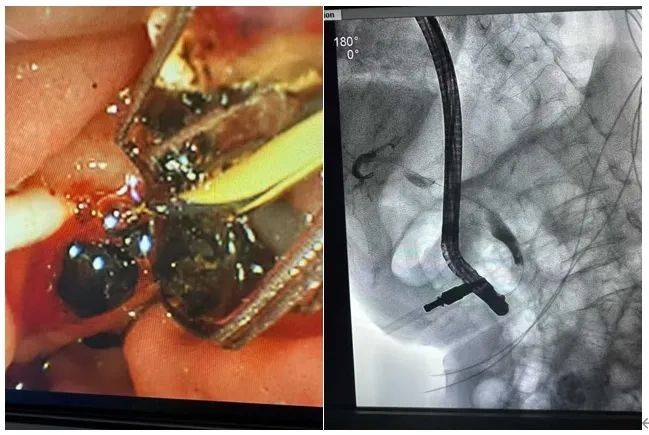

肝胆胰外科为99岁老人成功完成ERCP手术

近日,我院肝胆胰外科成功为一位99岁高龄老人实施了ERCP手术(内镜逆行胰胆管造影),在不需要开刀的情况下,精准取出嵌顿的胆总管结石,解除胆道阻塞,挽回患者濒临失控的病情。

患者因反复腹胀、皮肤巩膜黄染、进食困难入院,影像检查提示:胆总管结石梗阻、梗阻性黄疸,情况危急。若不及时解除梗阻,极可能发展为胆源性败血症,危及生命。但传统手术或全麻下微创手术对一位接近百岁的老人来说,风险几乎不可能承受,ERCP成为唯一的方案。

99岁意味着患者心肺储备能力极低,稍有波动便可能出现不可逆的并发症;意识易波动,配合度难以保障;麻醉、镇静容错率极低;操作空间几乎不容许“试错”。在这样的背景下,ERCP的每一次推进内镜、每一次导丝通过、每一次取石操作,都必须快、准、稳。

在麻醉科、重症监护团队的密切协同下,肝胆胰外科团队在患者清醒状态下,仅用20分钟就顺利为其完成取石及引流操作。

术后患者状态良好,黄疸逐步缓解,进食恢复。